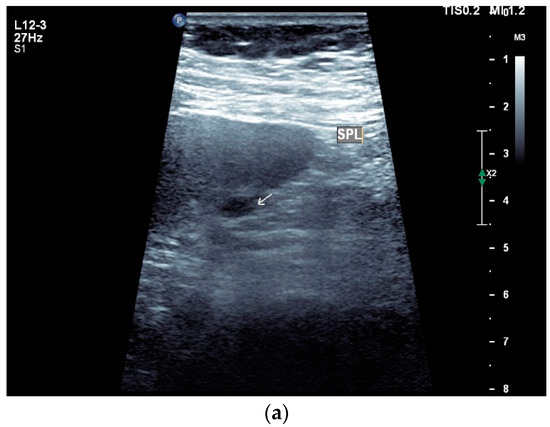

Figure 4.

Sonographic and CEUS features of splenic tuberculosis. Sonographic and CEUS features of splenic tuberculosis. Subcapsular splenic lesion (arrow) (a), subcapsular splenic lesion using a linear transducer of 12 MHz (arrows) (b). Histologically confirmed tuberculosis from mediastinal lymph nodes. Multiple small splenic lesions (c). Using CEUS with a linear transducer (9 MHz), these are slightly hypoenhanced in the arterial phase (d), and show a progressive washout in the course of the venous phase (arrows) (e). Subcapsular splenic lesion (arrow) with nonenhanced and hypoenhanced parts and hyperenhanced rims indicate a caseous necrosis (f). In another section, an interrupted spleen capsule (arrow) due to a rupture of the caseous necrosis can be assumed (g).